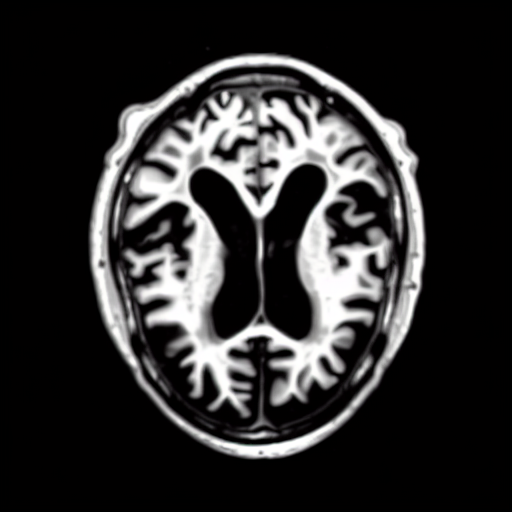

We present the results of conditional medical image generation with and without our proposed method LD, in Tab. 1, and Fig. 5. In Fig. 4, we show examples of brain MR images generated by the different methods combined with LD for two different classes of cognitively normal (CN) and Alzheimer’s disease (AD). The results were obtained by fine-tuning the corresponding method on the medical data with LD. As shown in Fig. 4, the samples generated through Custom Diffusion tuning are realistically looking while understanding the difference between CN and AD brain properly, which other methods failed at. Textual inversion seems to understand the concept but fails to understand the brain structure properly. Quantitative results on the performance of all our methods are presented in Tab. 1. Qualitative results on the CheXpert [19] dataset, along with a user study and ablation of different parameters, optimization algorithm, and more, are included in the supplementary material.

Qualitatively, Fig. 5 shows a significant improvement of the visual realism across all methods when using a drift of . The background is consistently black as in real brain MR images; the shape of the brain becomes more realistic, and the white and gray matter structure improves. For an analytical evaluation, we calculated the FID between our test data and 200 synthetically generated images from each method (100 CN, 100 AD). The results in Tab. 1 demonstrate that LD improves the ability of the model to generate realistic MRI slices for both healthy brains and brains with Alzheimer’s disease. For this reason, all following experiments were done with LD.